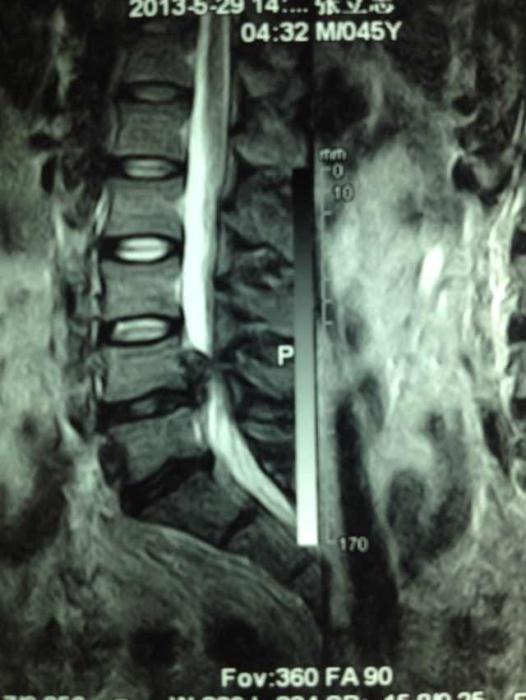

A术前

图1:A术前

如今,在疼痛病房经常看到患者脸上洋溢着满意的笑容。占恭豪主任说,上述三位患者的腰椎都是巨大突出,张先生的突出物似门帘下垂;李先生的腰椎突出物似尾巴上翘,陈公公的是两节的腰椎巨大突出,神经都严重的受压,导致日常活动明显受限,生活质量严重下降。

腰椎间盘突出症的原因是腰椎骨中央髓核从包围它的纤维环裂口往外涌,形成一个凸起物,压迫腰椎神经,引起腰腿疼痛及麻木感,如果拖延下去,可导致下肢麻木发凉、酸困不适、抽筋、腿部肌肉萎缩、力量减弱、下肢不能抬离、甚至大小便异常。椎间孔镜就是在内窥镜下,使用抓钳摘除突出的组织。